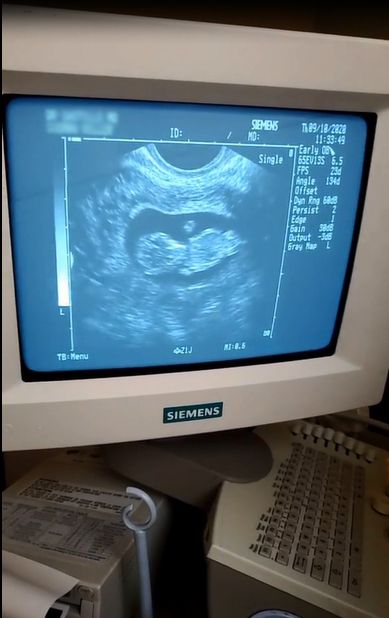

Baby超音波紀錄 : 11週 Posted on September 13, 2020 by yourtesttubebaby 11週的小baby就是長的這樣的! 寶寶營養很好所以長得很快而且蠻大隻的! !😄 ☀ 網站上每位小寶貝都是我們的成功案例,照片皆經父母親許可使用 ( 若未經允許請勿轉載 ) ☀ Posted in Uncategorized